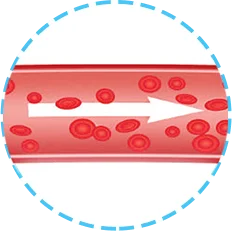

Los vasos llevan sustancias alimenticias y oxígeno a los órganos y tejidos.

El aumento del nivel de colesterol en la sangre puede indicar la formación de placas en los vasos.